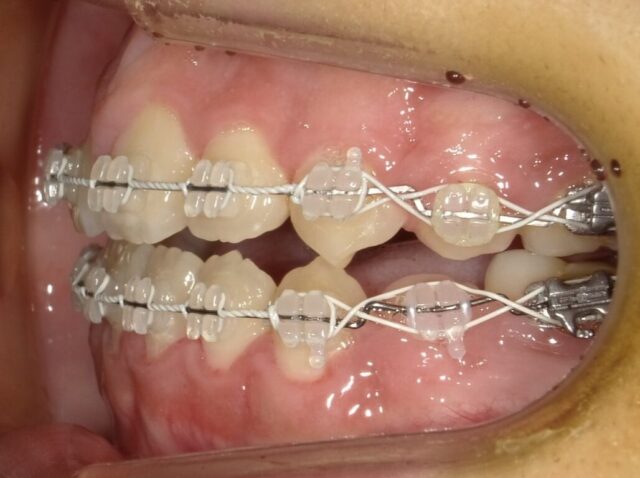

≪左側面観≫

2023年5月

2023年6月